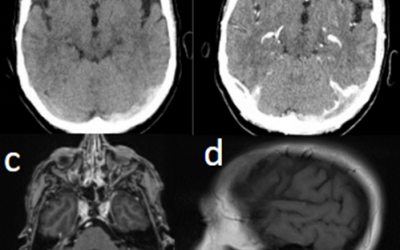

Caso del mes Abril 2026

« Todos los casosAutores Adrián Marín Rodríguez, Gonzala Fernández de Troya, Carmen González Soto....